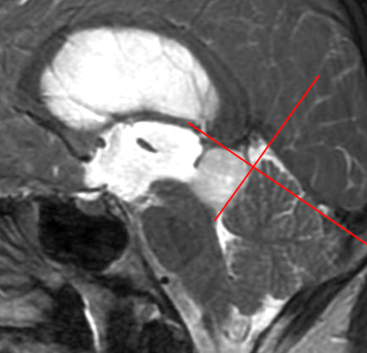

35岁的Emma,中脑顶盖肿瘤,内生性生长,仿佛被脑组织严密包裹,所幸尚未突破脑干表面。

术前MRI

巴教授选择了幕下小脑上旁中央入路,面对这个“很有弹性,容易‘溜走’”的肿瘤,巴教授手持CUSA刀(超声吸引器),击碎肿瘤然后再吸走。正常脑组织完好无损,而肿瘤被成功切除。

术后,患者短暂出现了帕里诺综合征,术后8周自行缓解。最终,病理报告显示:形成菊形团的胶质神经元肿瘤(RGNT)。术后5年随访时,MRI显示肿瘤无复发。术后12年的长期随访显示,她依然状态良好!